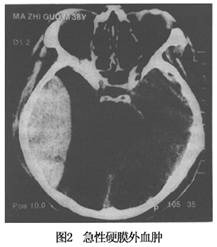

CT表現爲呈雙凸鏡形密度增高影,邊界銳利,骨窗位可顯示血腫部位顱骨骨折。同側腦室系統受壓,中線結構向對側移位(圖2,3)。

幕上急性硬膜外血腫的早期診斷,應判定在顳葉鉤回疝徵象之前,而不是昏迷加深、瞳孔散大之後。故臨牀觀察尤爲重要,依據頭部外傷史,着力部位及受傷性質,傷後臨牀表現,早期X線顱骨平片等,可對急性硬膜外血腫做初步診斷。當病人頭痛嘔吐加劇、躁動不安、血壓升高、脈壓差加大和(或)出現新的體徵時,即應高度懷疑顱內血腫,及時給予必要的影像學檢查,包括X線顱骨平片、CT掃描等。其中CT掃描是首選輔診方法,不但能明確診斷,而且能準確反映血腫部位、大小、佔位效應、合併腦內損傷等,爲手術提供可靠的依據。